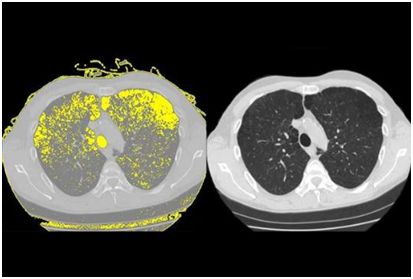

3.HIV 治疗的背后:HIV 如何一步步将患者的肺摧毁!

doi:10.1016/j.celrep.2017.04.026

高达 30%的接受抗逆转录病毒疗法治疗的艾滋病毒患者发展为慢性肺病肺气肿。 Weill Cornell 医学研究人员的新研究发现了一种可能解释为什么会发生肺损伤的机制。

研究人员在“细胞报告”5 月 9 日发表的研究报告中显示,人类免疫缺陷病毒或 HIV 与干细胞结合,称为基底细胞,其转化为其他类型的细胞。该过程重新编程基底细胞,导致它们释放被称为蛋白酶的酶,其可以破坏肺组织并在进行氧气交换的空气囊的壁中戳出孔。

为了进行这项研究,调查人员将正常的人气道基底细胞从健康非吸烟者的肺部收集,并在观察下暴露于艾滋病毒一段时间。将病毒与基底细胞表面结合并重新编程,以开始产生可以分解蛋白质并破坏组织的酶或蛋白酶,称为金属蛋白酶 -9。因为研究人员知道肺气肿是气道疾病,这一发现表明,当基底细胞呈现称为“破坏性表型”的晶型时,他们开始在健康组织中消失,这会及时得导致肺气肿。

“看病毒如何改变细胞的功能是一个重要的观察方面,”Crystal 说,他提到 Zika 病毒通过感染神经干细胞和改变其功能以类似的方式运作,这导致了一个出生缺陷,其特征为小于正常头部和异常脑,称为小头症。